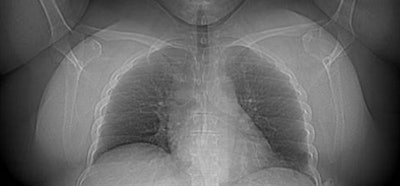

![]() |

| Heavy patients were scanned successfully. Scout image of a 56-year-old woman weighing 305 lb (BMI, 54) shows a large amount of subcutaneous fat. Despite substantial image noise, coronary CTA was diagnostic and all arteries were assessable and patent. Images were acquired at 800 mA, 120 kV, and an effective dose of 3.2 mSv. All images courtesy of Dr. James Earls. |